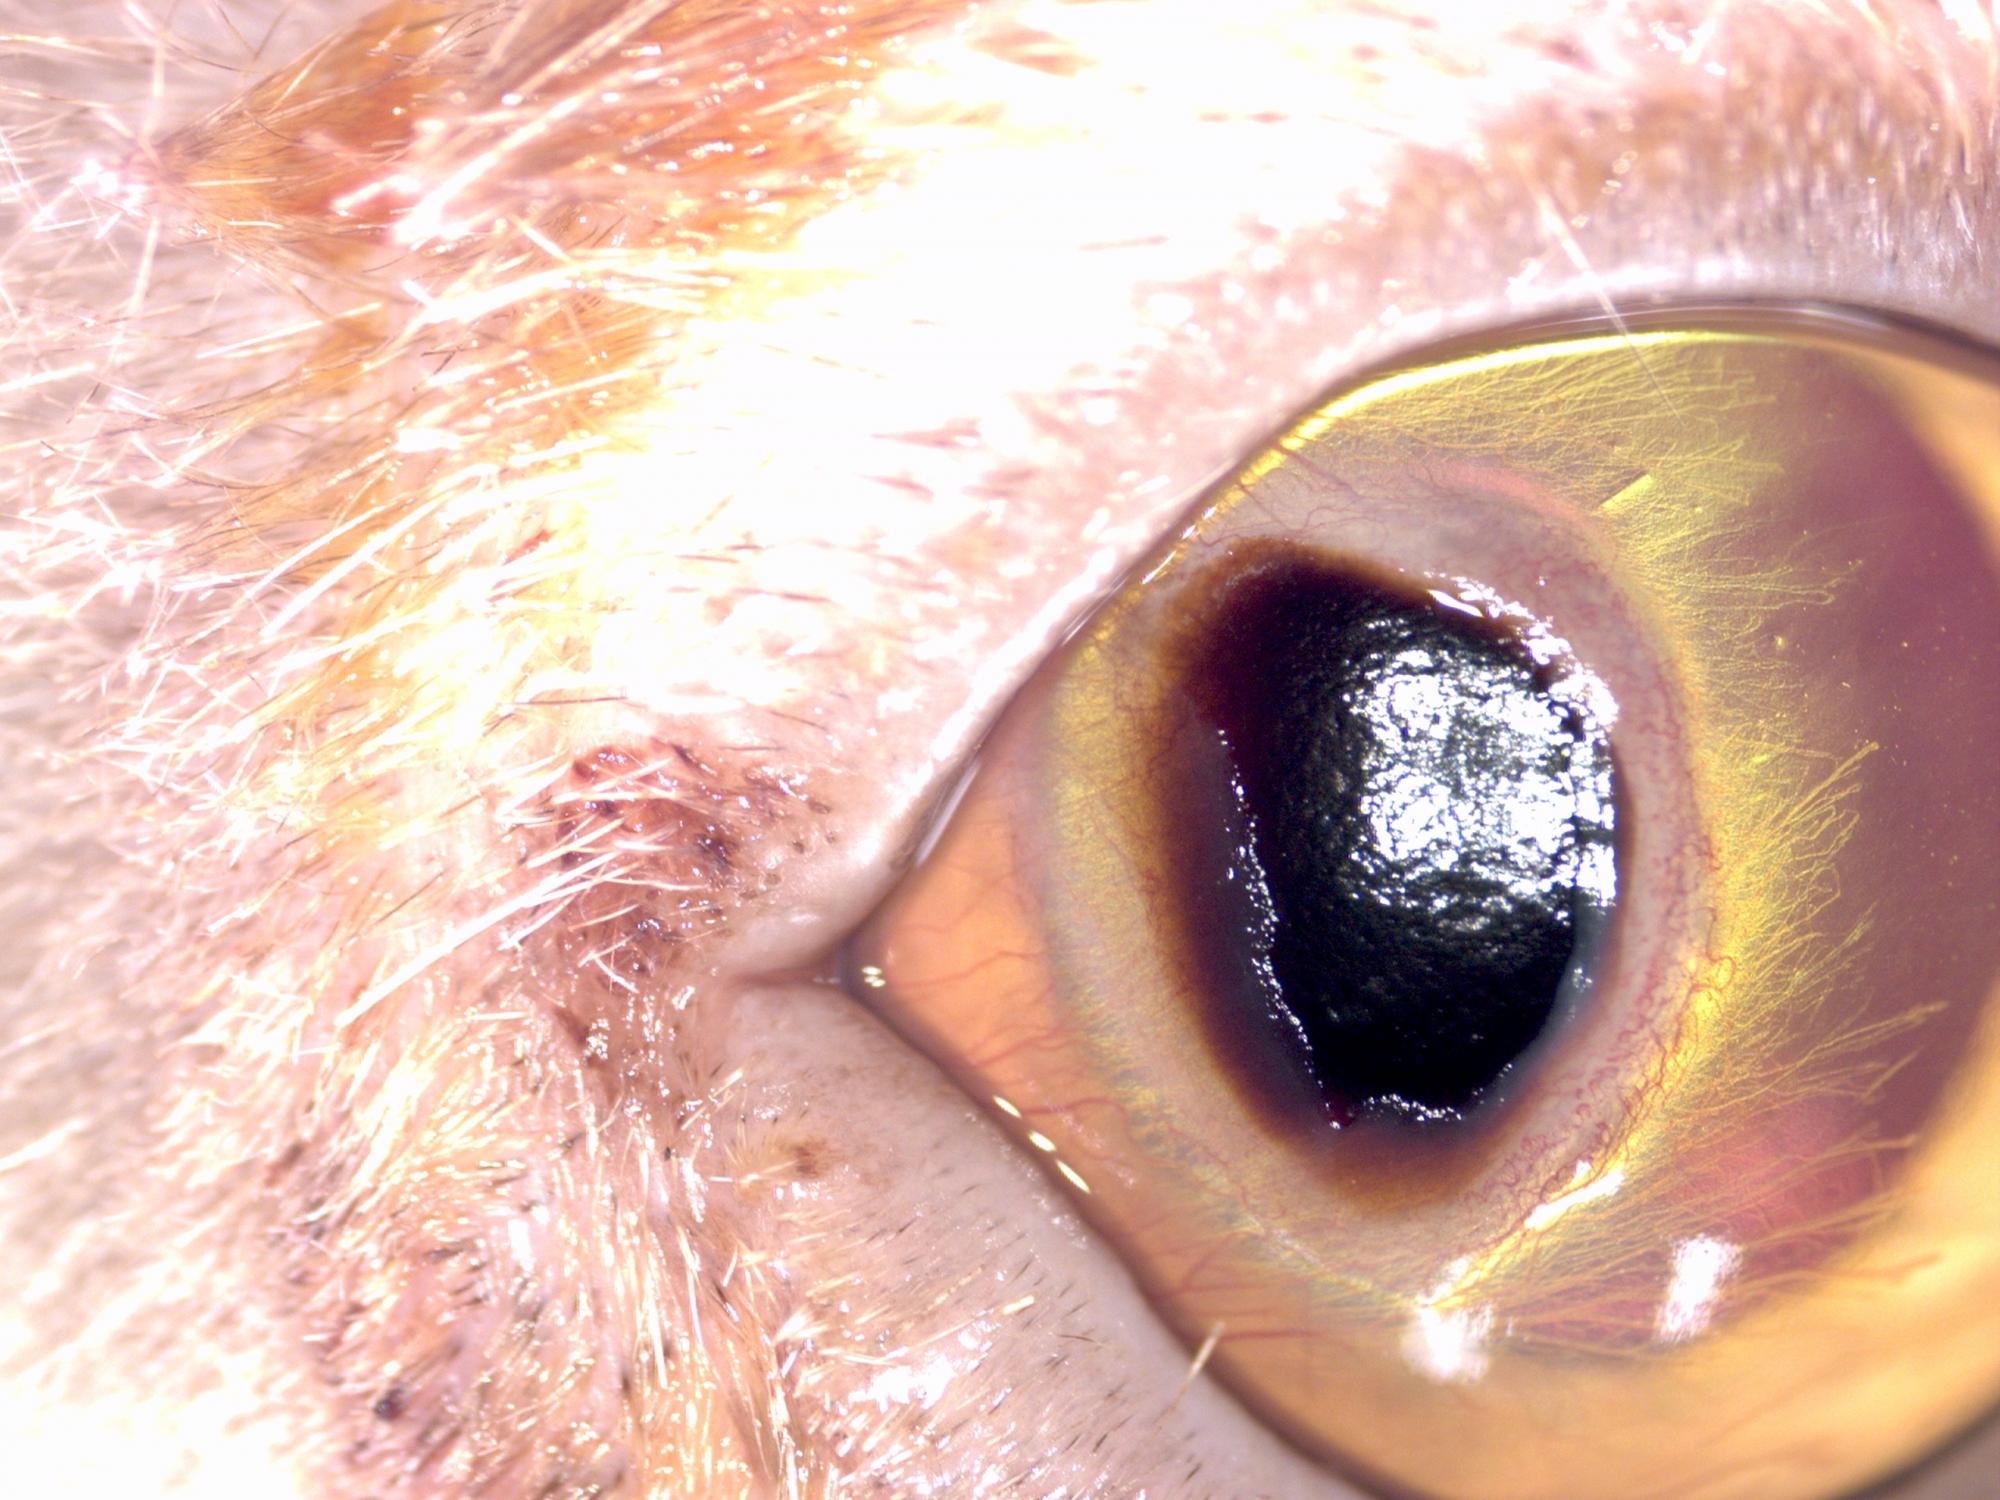

Na fotografiích je kočka před operací, v průběhu operace - lamelární keratektomie a 2 týdny po operaci.

Spastické entropium. Bolestivý stav na oku vedl k chlípení víčka a k dalšímu zhoršení stavu rohovky iritací chlupy. | Veterinární klinika Medipet Zlín

Tmavě pigmentovaný sekvestr se zánětem rohovky a výraznou vaskularizací. | Veterinární klinika Medipet Zlín